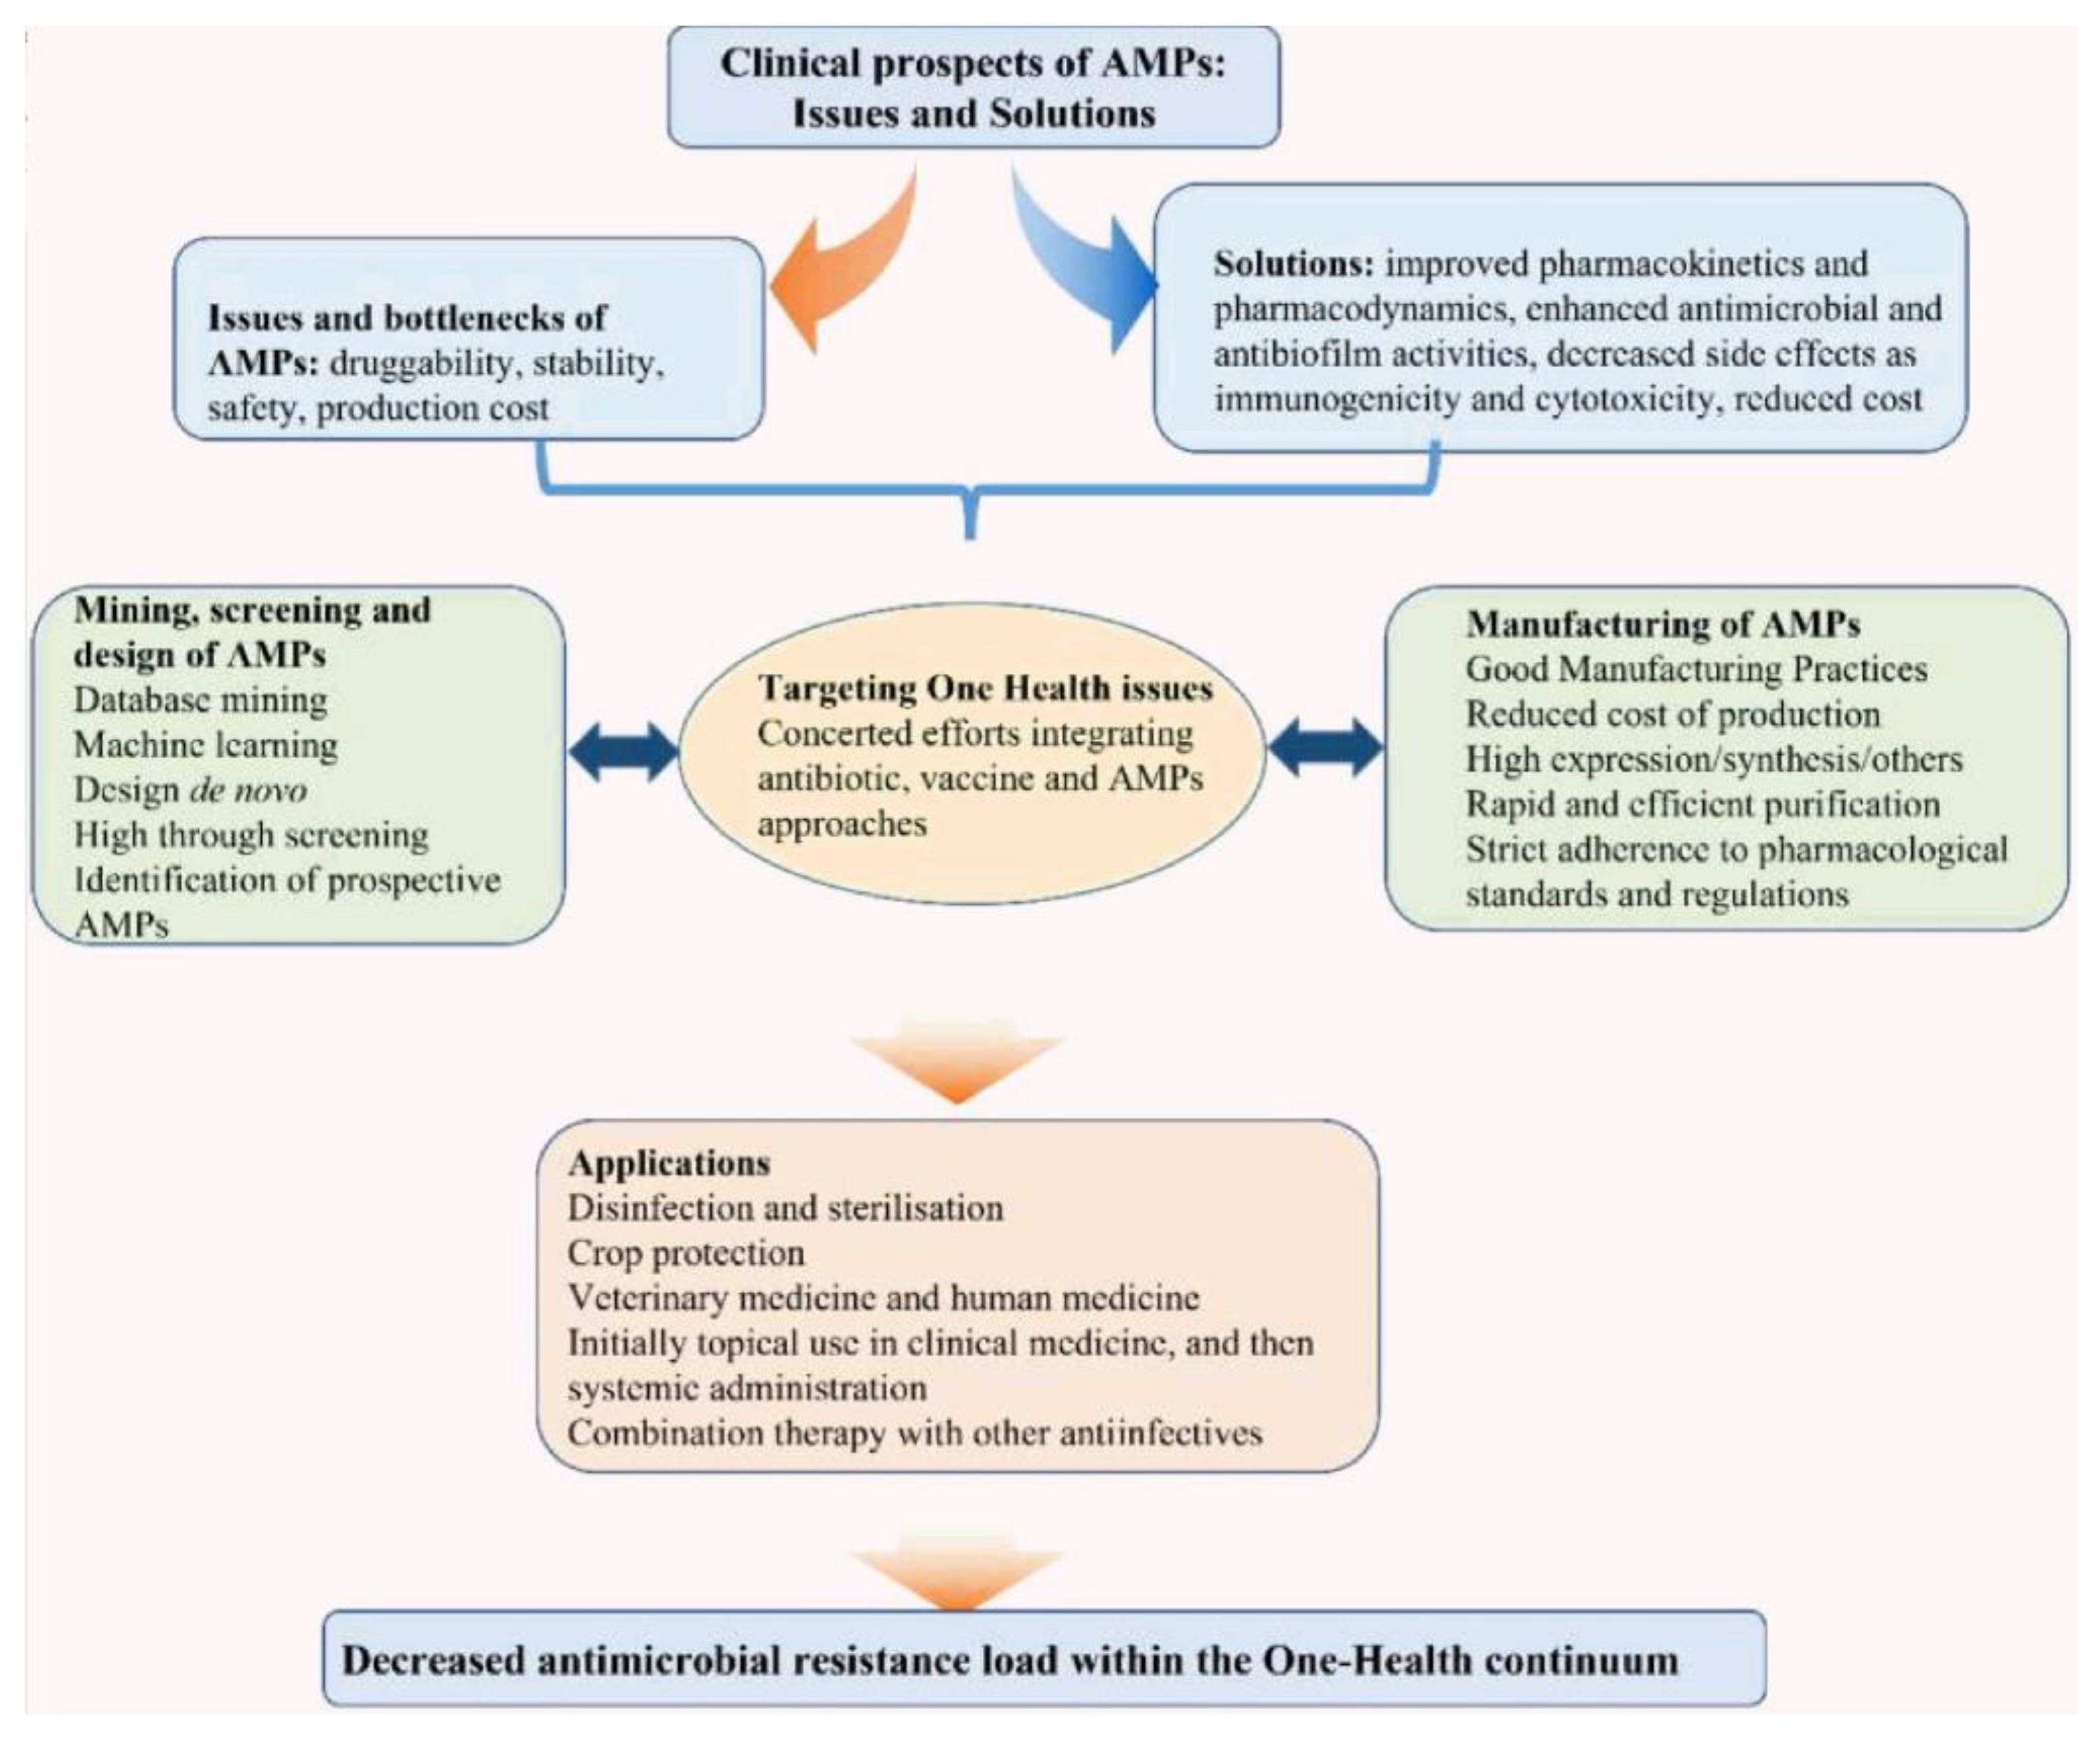

5. Conclusions